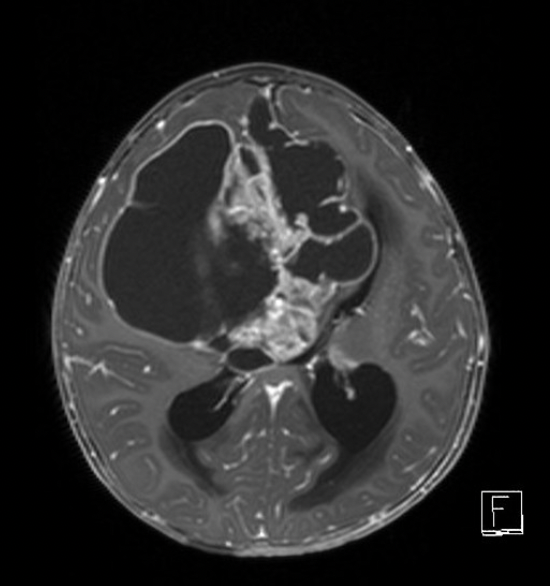

Imagem 2

Intoxicação pelo metotrexate